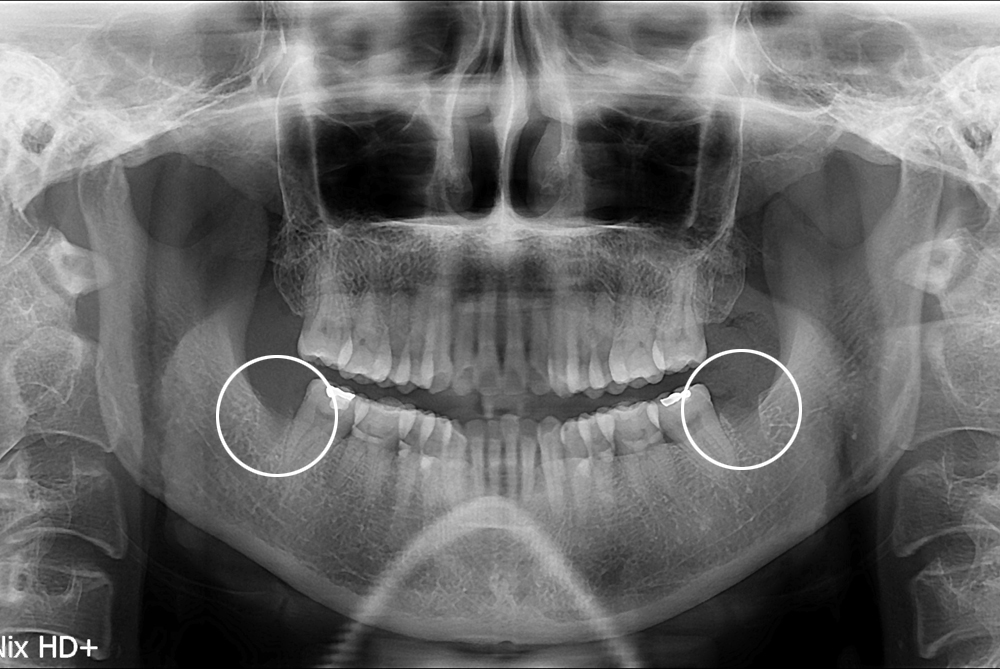

치료후 : 2017-01-10

세종치과는 구강악안면외과학 박사이신 원장님이 발치하는 치과입니다.